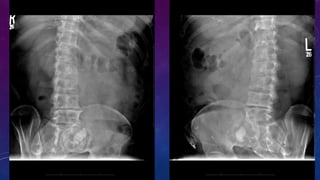

• Multiple pelvic phleboliths.

• Small well-defined round osseous lesions in the left

side of the abdomen, adjacent to midline represent

calcified lymph node in the para-aortic and left

common iliac groups, also visualized on the

corresponding CT.